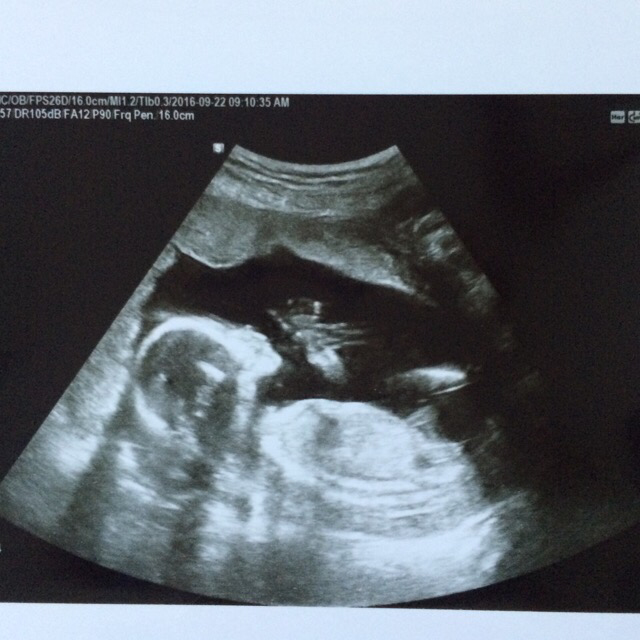

17주 초음파 검사

이어서 초음파 검사! 초음파 검사를 기다리며 엄마 손 꼭 잡고 검사 침대에 누워있으니 의사 선생님이 씩 웃으며 떨리냐고 물어보신다. 딱히 아프거나 이상한 증상은 없더라도 초음파 검사 전에는 항상 떨린다.

어느새 더 쑥- 커버린 우리 행복이.

'엄마 안녕' 하고 손 흔들 듯 다섯손가락을 쫙 펴고 있다니.

콧대가 제대로 잘 생겨야 한다는데, 잘 보이게 옆태를 보여주어 고맙다. 턱선과 콧대에 뿅!

중국의 병원보다 친절하고 상세한 설명을 들을 수 있었다. 중국-한국을 오가며 검사를 받고 있어 뭔가 불안한 마음이었는데, 얼마 후 있을 임당 검사만 필수로 잘 챙겨 받으면 된다고 안심시켜주셨던 의사 선생님. '앞으로 행복이 태어날 때까지 잘 부탁드려요.'